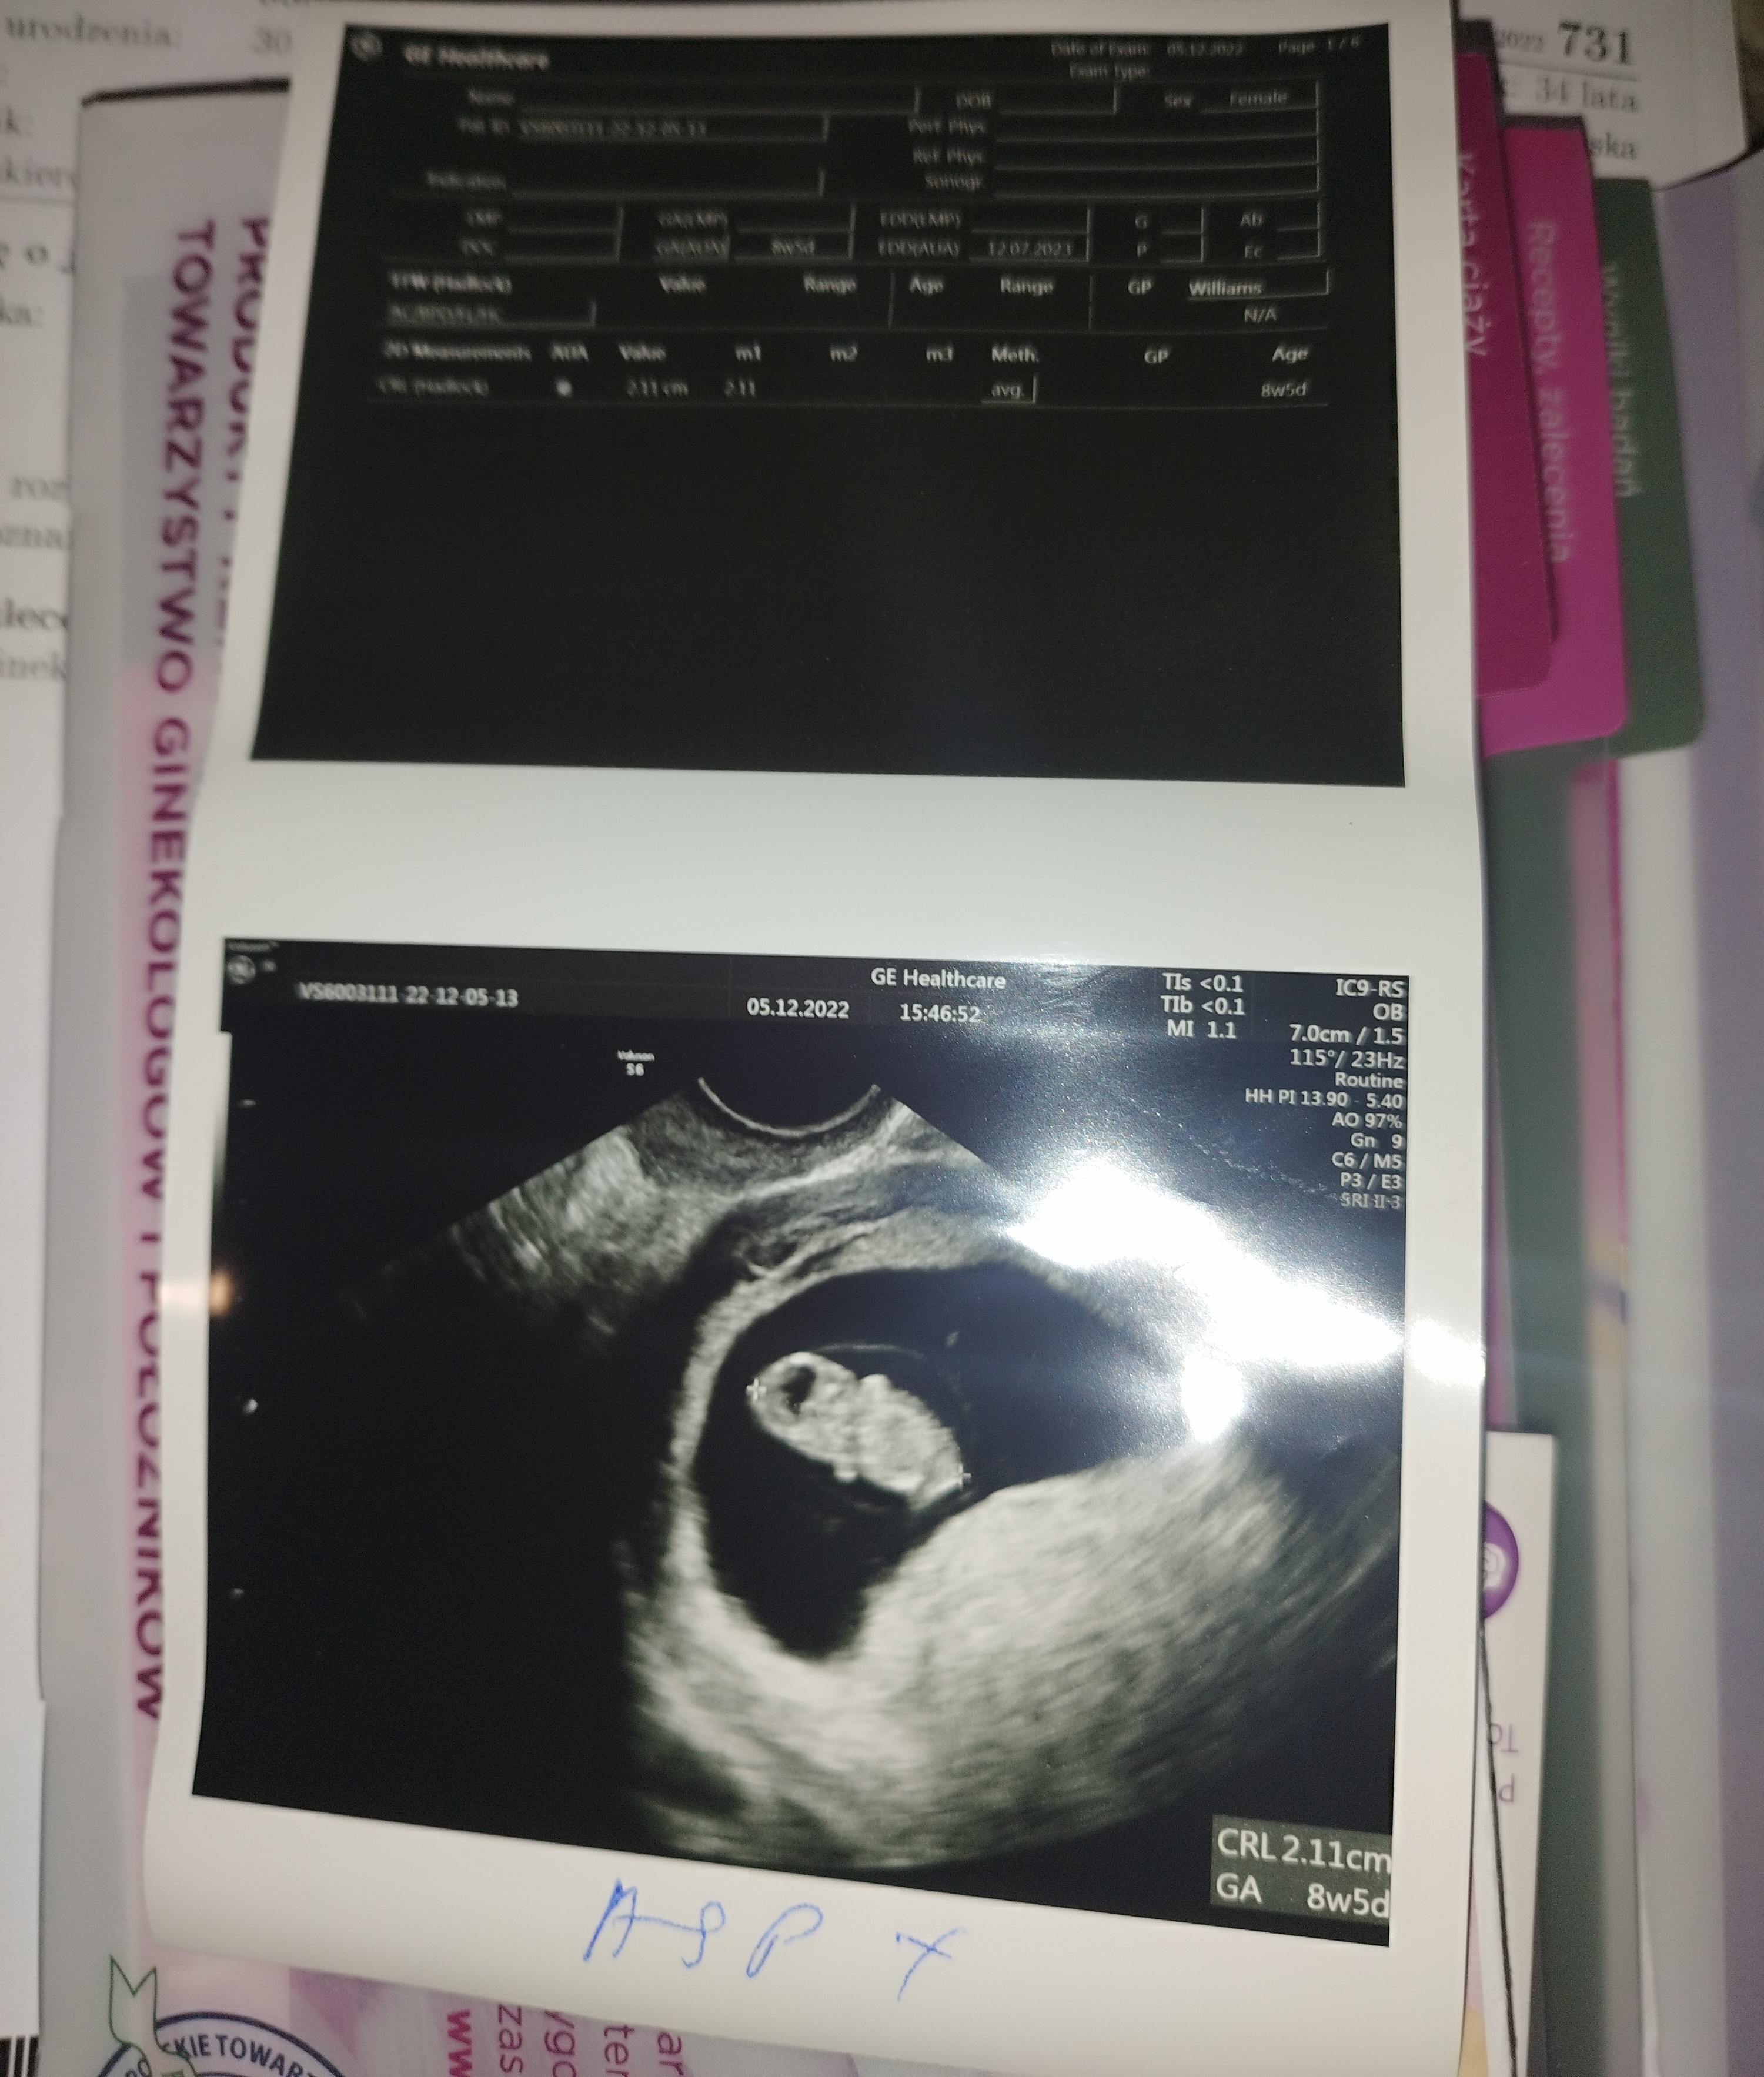

Tak, poproszę!Moja ginekolog w Tychach robi prenatalne, ma cert fmf, ja jestem z niej bardzo zadowolona, ale też jestem jej pacjentkąjeśli chcesz podeślę Ci nazwisko , jeśli wszystkich traktuje jak swoich stałych pacjentów (a nigdy nie wiadomo) to będziesz zadowolona, przemiła, fachowa lekarka